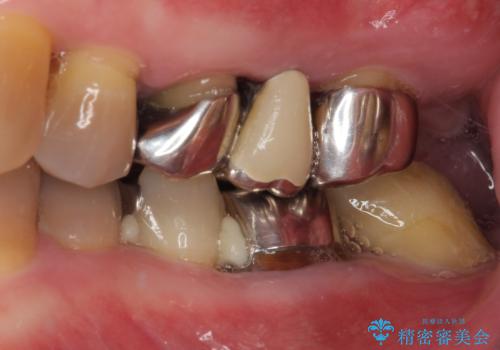

上下ともに前歯のセラミッククラウンによる補綴治療を希望されていましたが、下顎前歯は叢生が強いため、補綴治療前に部分矯正を行って歯列を整えた上で、補綴治療を行うこととしました。

臼歯部には歯周ポケットのある箇所が散見されましたが、まずは前歯を治療したいとのことで、治療を進めました。

ディープバイトにより臼歯部に負担のかかる咬合であったので、補綴治療後には、矯正治療の後戻り防止もかねて、睡眠時にマウスピースを装着するように指示しました。